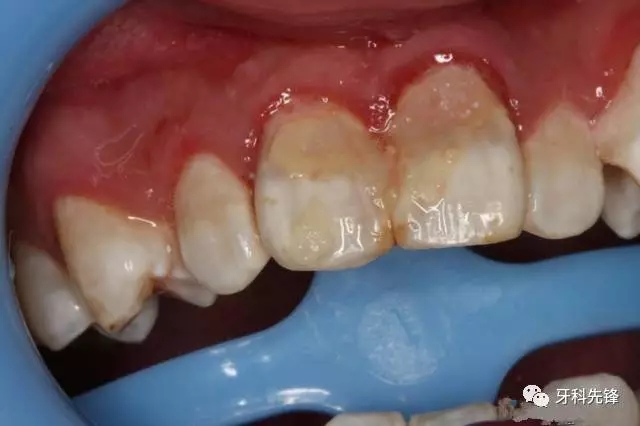

圖3.術(shù)前患者口內(nèi)像,12、11松動(dòng)Ⅱ°,21松動(dòng)Ⅰ°。